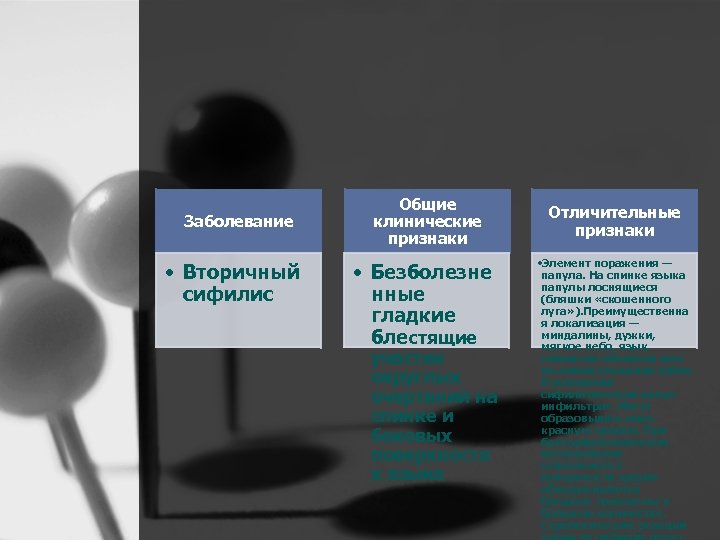

Заболевание • Вторичный сифилис Общие клинические признаки • Безболезне нные гладкие блестящие участки округлых очертаний на спинке и боковых поверхностя х языка Отличительные признаки • Элемент поражения — папула. На спинке языка папулы лоснящиеся (бляшки «скошенного луга» ). Преимущественна я локализация — миндалины, дужки, мягкое небо, язык, слизистая оболочка щек по линии смыкания зубов. В основании сифилитических папул инфильтрат. Могут образовывать мясо красную эрозию. При бактериоскопическом исследовании отделяемого с поверхности эрозии обнаруживаются бледные трепонемы в большом количестве. Серологические реакции